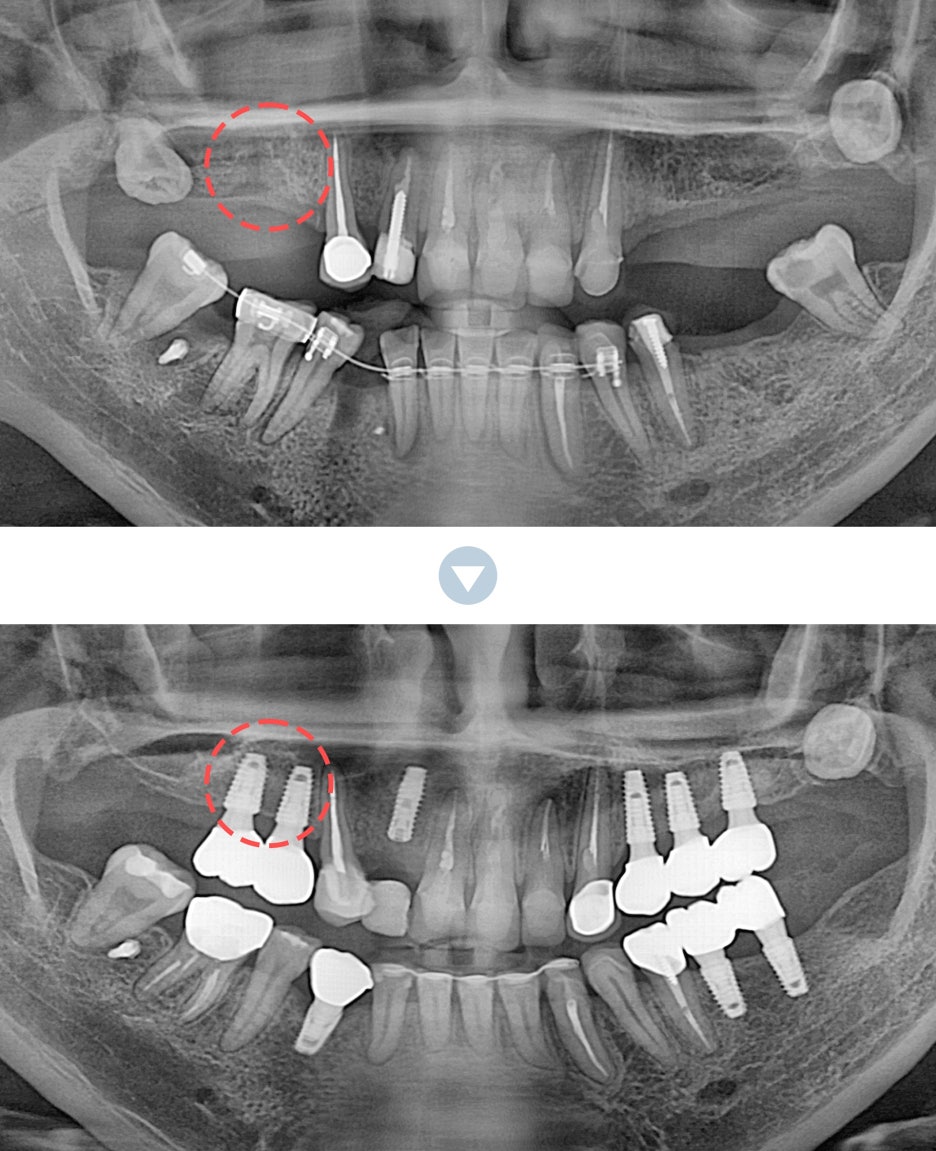

특히 위쪽 어금니 쪽이 상실 되어 임플란트 시술을 진행해야 하는데 잇몸 뼈가 부족한 상태라면 추가적으로 상악동거상술을 함께 진행해야 했어요. 상악동이란 코 양옆에 위치하고 있으며 뼈 속에 비어 있는 공기 주머니로 두개골의 무게를 줄여주는 곳이었어요. 상악동은 아주 얇은 막으로 둘러 쌓여 있으며 상악 쪽의 잇몸 뼈가 부족한 상태로 임플란트를 식립 하게 된다면 상악동 막이 찢어지거나 천공이 생길 수 있었어요.

상악동에 천공이 생기게 된다면 염증으로 인해 부작용이 생길 수 있었어요. 그렇기 때문에 환자 개개인마다 크기와 위치가 모두 다른 상악동의 위치와 잇몸 뼈의 두께를 정확히 파악하는 것이 중요했어요. 정밀 검사 후 임플란트를 식립 하기에 잇몸 뼈의 양이 부족하다는 진단이 나오게 된다면 얇은 상악동 막을 들어올려 준 후 필요한만큼의 뼈 이식을 진행해 주는 방법이 상악동거상술이었어요.

신논현역임플란트에서 말하는 상악동거상술은 치조정접근법과 측방접근법인 두가지 방법으로 진행할 수 있었어요. 남아 있는 잇몸 뼈의 양에 따라 이식 해야 하는 양이 달라지고 그로 인해 상악동에 접근 하는 방법을 기준으로 두가지 방법은 나눠 지고 있었어요. 먼저 치조정접근법은 잇몸 뼈가 4-8mm 정도 확보 되었을 때 사용하는 방법으로 치아가 상실 된 위치의 잇몸에 작은 구멍을 뚫어 준 뒤 그 구멍을 통해 상악동 막을 들어 올린 후 뼈 이식을 진행하는 방법이었어요.

작은 절개 범위와 뼈 이식 양이 많지 않기 때문에 수술 시간이 짧고 통증과 붓기도 적으며 회복 속도 또한 측방접근법에 비해 빠른 편이었어요. 반면 측방접근법은 잇몸 뼈가 4mm 이하로 많은 양의 잇몸 뼈를 이식 해야 할 때 필요한 방법이었어요. 잇몸 측면에서 큰 창 모양으로 절개 후 접근하는 방법으로 수술시간이 길고 붓기, 통증이 큰 편으로 회복 속도 또한 더딘 편이었어요.

하지만 시야 확보가 잘 되어 출혈과 돌발 상황에 대한 대처를 빨리 할 수 있어 안전하게 수술을 마무리 할 수 있다는 장점이 있었어요. 치조정접근법과 측방접근법 두가지 방법 중 어떠한 방법이 더 유리하고 안전하다고 할 수 없으며 치조골의 상태와 식립 해야 하는 임플란트의 개수, 상악동의 위치와 두께 등을 고려하여 환자분께 적합한 방법으로 상악동거상술을 진행 하는 것이 가장 안전하고 좋은 방법이라고 할 수 있었어요.

이러한 구강 상태를 확인하기 위해서는 여러가지 디지털 입체 장비를 통해 정밀 검사를 진행한 후 정확히 파악하는 것이 중요하며 그에 맞춰 적합한 방법으로 진단한 후 체계적으로 치료 계획을 수립 해야 했어요. 의료진의 진단과 시술 경험에 따라 치료 결과는 크게 달라질 수 있기 때문에 상악동거상술을 동반한 임플란트 시술을 안전하고 성공적으로 마치기 위해서는 치과를 선택할 때 꼼꼼히 따져본 후 치료를 시작하는 것이 바람직한 방법이었어요.

신논현역임플란트에서는 3D 구강스캐너와 CT 등 다양한 전문 장비로 구강상태를 정밀하게 입체적으로 확인하고 환자분과 상담을 통해 상악동거상술의 치료 계획을 세우고 있었어요. 상악동거상술은 치과 치료 중에서도 난이도가 높은 치료에 속하기 때문에 환자분께서는 부담스럽고 두려우실 수 있었어요. 무턱대고 당장 치료를 시작하기 보다는 신논현역임플란트 잘하는 아름드리치과에서는 1:1 맞춤치료를 진행하며 환자분들과 충분한 상담을 통해 궁금증을 해결 해 드리고 통증과 부작용에 대한 우려를 덜어 드린 후 안심하고 진료 받을 수 있도록 의사소통을 활발히 하며 언제나 환자분을 우선으로 생각하며 진료하고 있었어요. 또한 얇은 상악동막이 찢어지거나 구멍이 나지 않도록 섬세하고 전문적인 실력이 뒷받침되어야 상악동거상술의 부작용을 최소화 할 수 있었어요.

아름드리치과는 상악동거상술을 동반한 임플란트 시술에 대해 다년간 쌓아온 경험을 바탕으로 노하우 뿐만 아니라 전문적인 실력을 갖추고 있어 안전하고 성공적인 시술 결과를 얻을 수 있었어요. 성공적으로 시술을 마친 후에는 오랜 시간 동안 건강하고 튼튼하게 유지할 수 있도록 신논현역치과 아름드리치과에서는 정기적으로 사후 관리를 진행해드리고 있으며 일상 생활 속에서도 꾸준히 치아 관리를 꼼꼼히 하실 수 있도록 설명 드리고 있었어요. 또한 상악동거상술을 마친 이후에 부작용이 생기거나 상태가 악화되지 않기 위해서 몇가지 주의사항을 지켜 주셔야 하였어요.